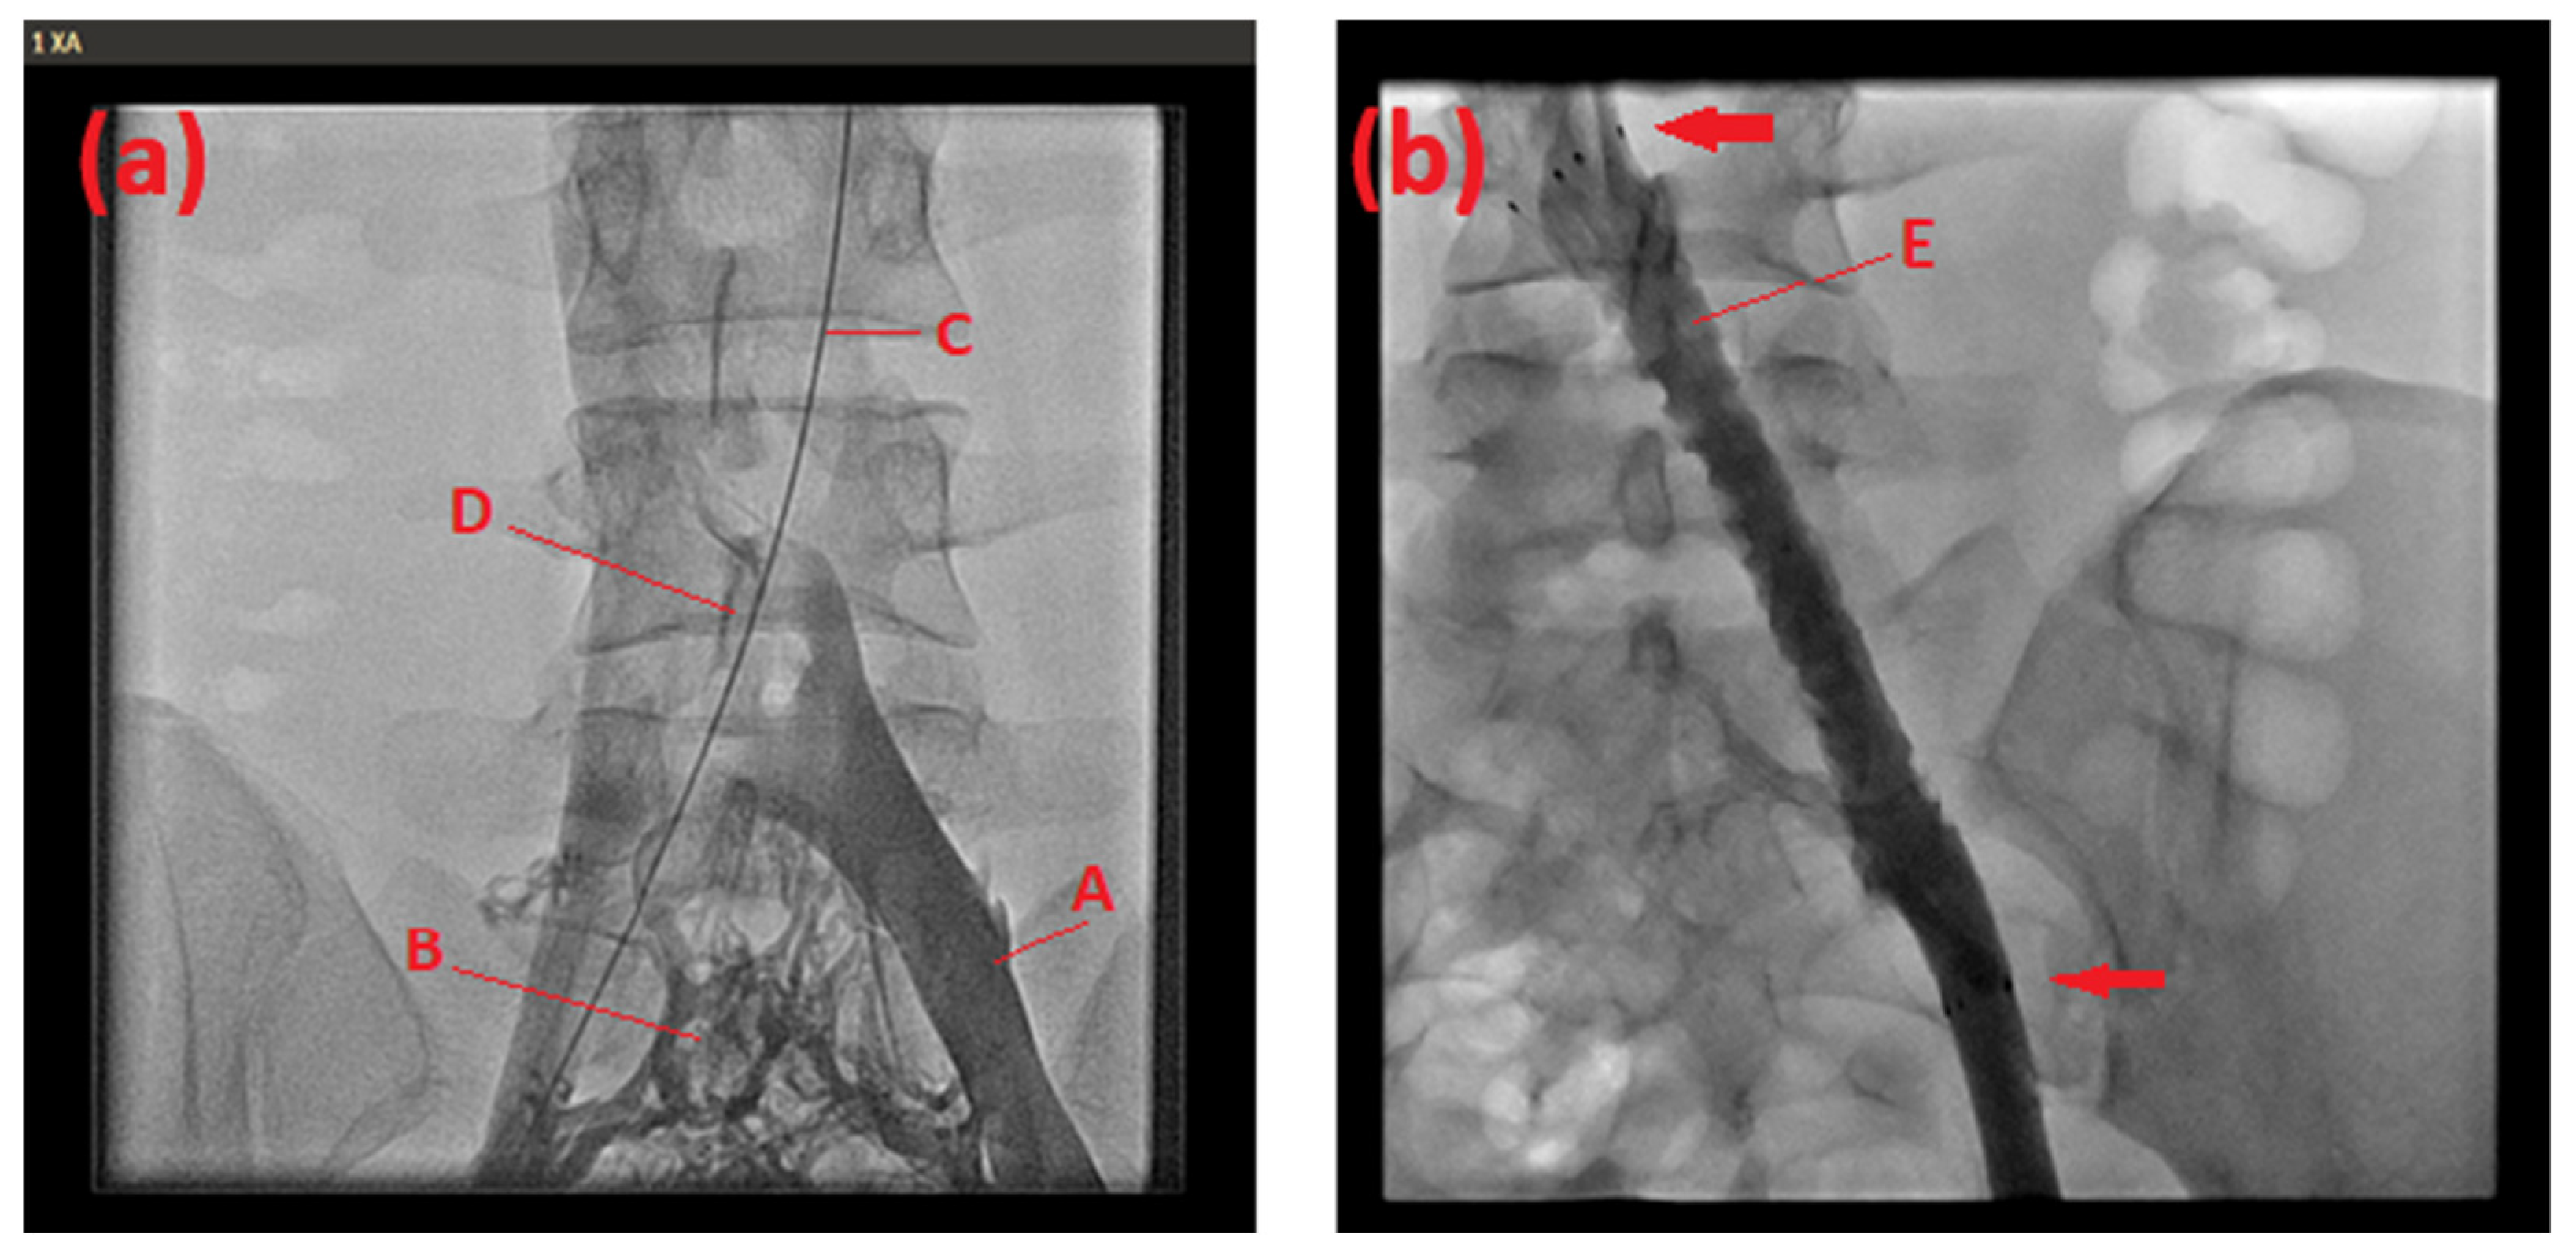

2.1. Case 1

2.2. Case 2

2.3. Case 3